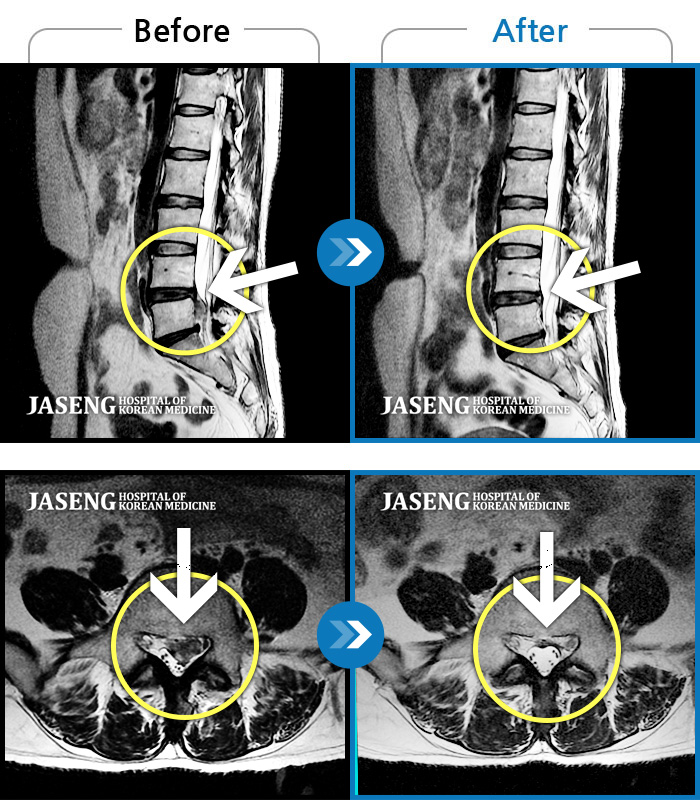

ȯںп Ǹ ǿ ԿǾ, ο ġ ۿ Ƿ ġḦ Ͻñ ٶϴ.